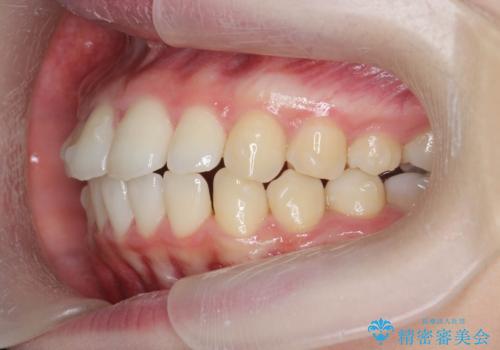

出っ歯を治すマウスピース矯正

- 出っ歯のように見える前歯の角度を治したい、と矯正治療を希望され来院されました。

抜歯をせずにマウスピース矯正システムインビザラインを用いてしっかりと前歯の角度を改善していきます。

前歯の角度だけでなく内側に倒れ込んでいた奥歯もしっかり起こすことで咬合関係も理想的に仕上げています。